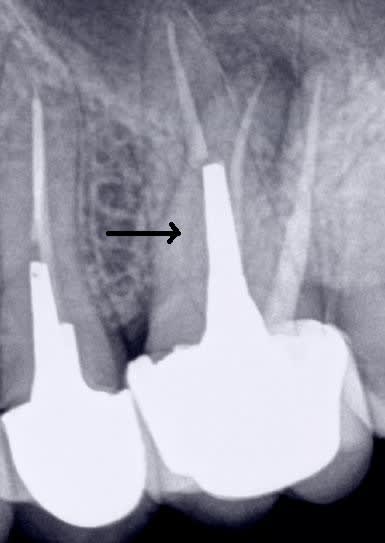

chicot29 écrivait:

> Meme sans digue et après 10 ans à l'air libre il n'y a pas de pèche à l'apex.

> Sauf si tu n'as pas traité le mv2.-))))

Radio 2 tu vois pas de pèche ?

Si justement. C'est bien le mv2 non traité. -)

Quand je vais la virer c'est ce que révèlera l'autopsie de cette racine. -)

Mais dans ce cas particulier c'est pas cette dent qui 10 ans après pose problème c'est la 15.-)

La couronne aurait au moins eu le mérite de protéger ce qui restait de la dent au départ. -)

Merde endo et couronne faites en 2011 pèche en 2017.

Quizzzzz : c'est la faute à pas de digue ? -))))